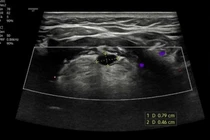

Nguyên nhân có thể do rối loạn hormone trong thai kỳ, bất thường nhiễm sắc thể hoặc cấu trúc tuyến sinh dục. Trẻ cần được xét nghiệm nhiễm sắc thể (XX hoặc XY), siêu âm tuyến sinh dục và đánh giá hormone để xác định giới tính thật.

Việc xác định đúng giới tính không chỉ quan trọng về mặt y học mà còn ảnh hưởng sâu sắc đến tâm lý, nhân dạng giới và cuộc sống tương lai. Nếu phát hiện sớm, phẫu thuật chỉnh hình và điều trị nội tiết có thể giúp trẻ phát triển bình thường như bạn cùng giới.